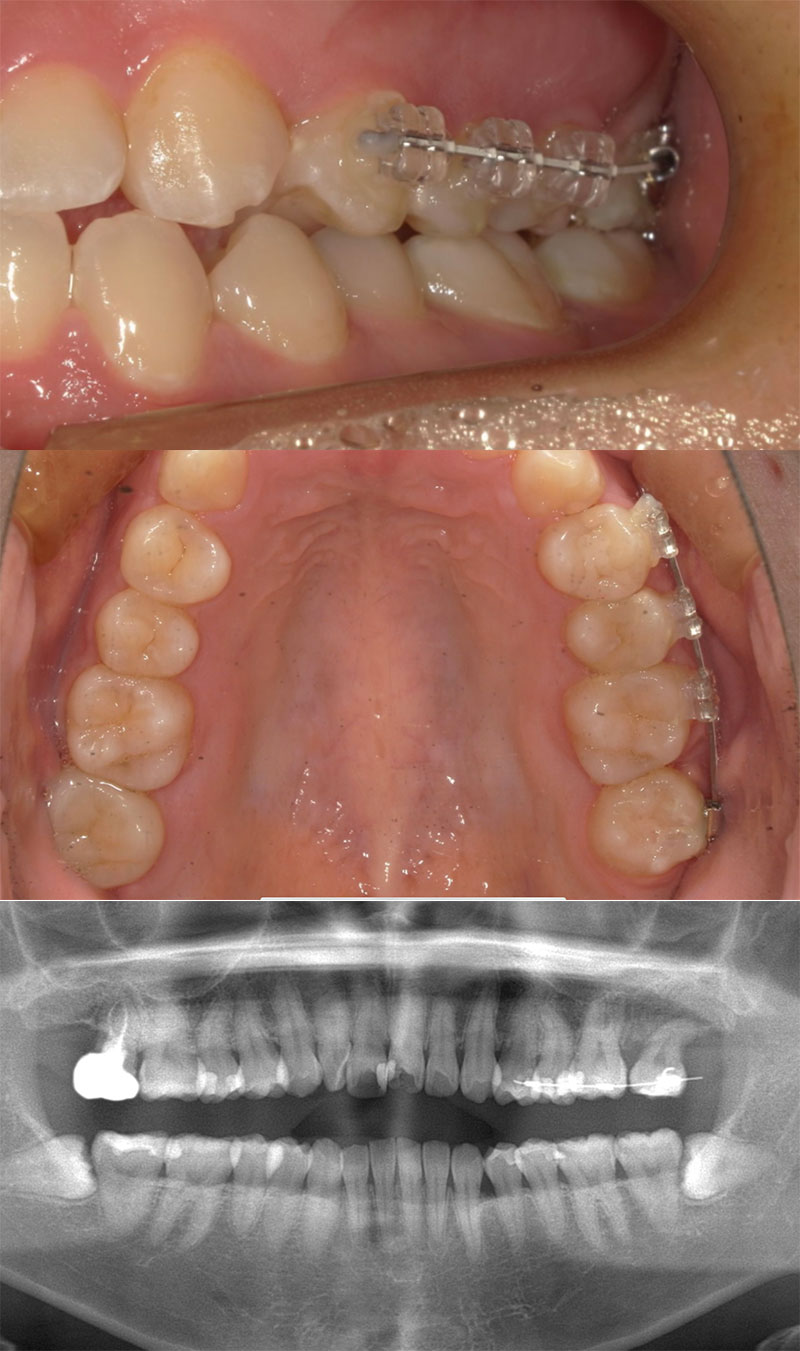

臼歯の部分矯正

親知らずの矯正症例になります。

前医で入れられた左上の第二大臼歯セラミックの歯の歯根が割れて膿んでいる状況で治すには抜歯しかなかった為、抜歯をしました。

抜歯後、親知らずが見えていたので牽引して動かすことができる状況でした。

通常保険診療では部分入れ歯や移植などが選択肢になってきますが、部分矯正MTMをご提案しました。

矯正で動かしてくることにより神経を温存し、ご自身の歯でお食事を楽しむことができるようになります。

患者さんも神経を取ってダメになったところがまた復活したと喜んでおられました。

| 患者様 | 30代女性 |

|---|---|

| 主訴 | 左上奥が噛むと痛い |

| 治療方法 | MTM矯正 |

| 治療費 | 125,400円(税込) |

| 治療期間 | 約4か月 |